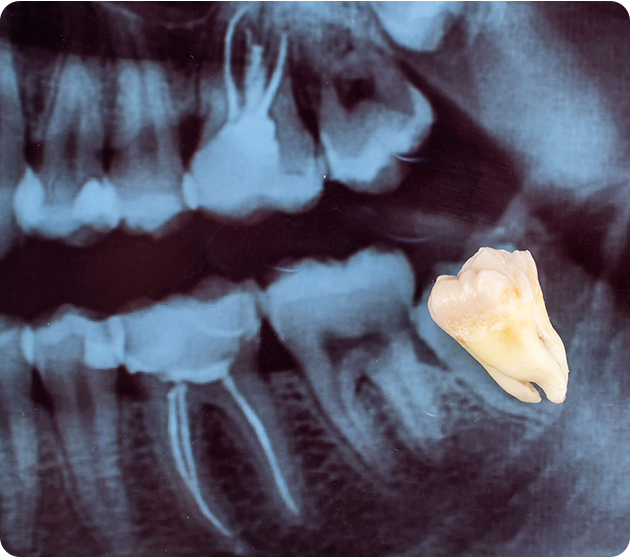

Wisdom teeth extraction is a common dental surgery performed to remove one or more third molars—known as wisdom teeth—that usually appear between the ages of 17 and 25. These teeth can cause issues if there isn’t enough space for them to grow properly.